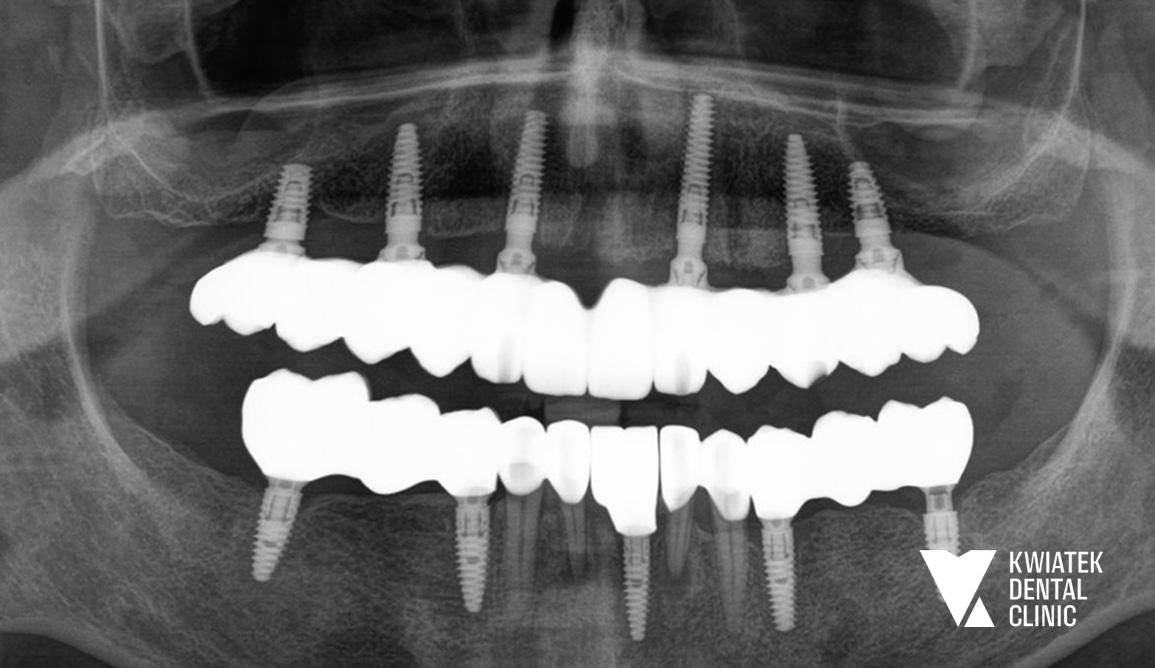

Kompleksowa odbudowa obu łuków zębowych na implantach

Pełna metamorfoza uśmiechu u Pacjenta, który dotąd korzystał z częściowej protezy. W łuku górnym wykonano odbudowę All-on-6, a dolny łuk zrekonstruowano za pomocą mostów na implantach i koron pełnoceramicznych. Efekt? Naturalny, stabilny uśmiech, który przywrócił pewność siebie i komfort na co dzień.